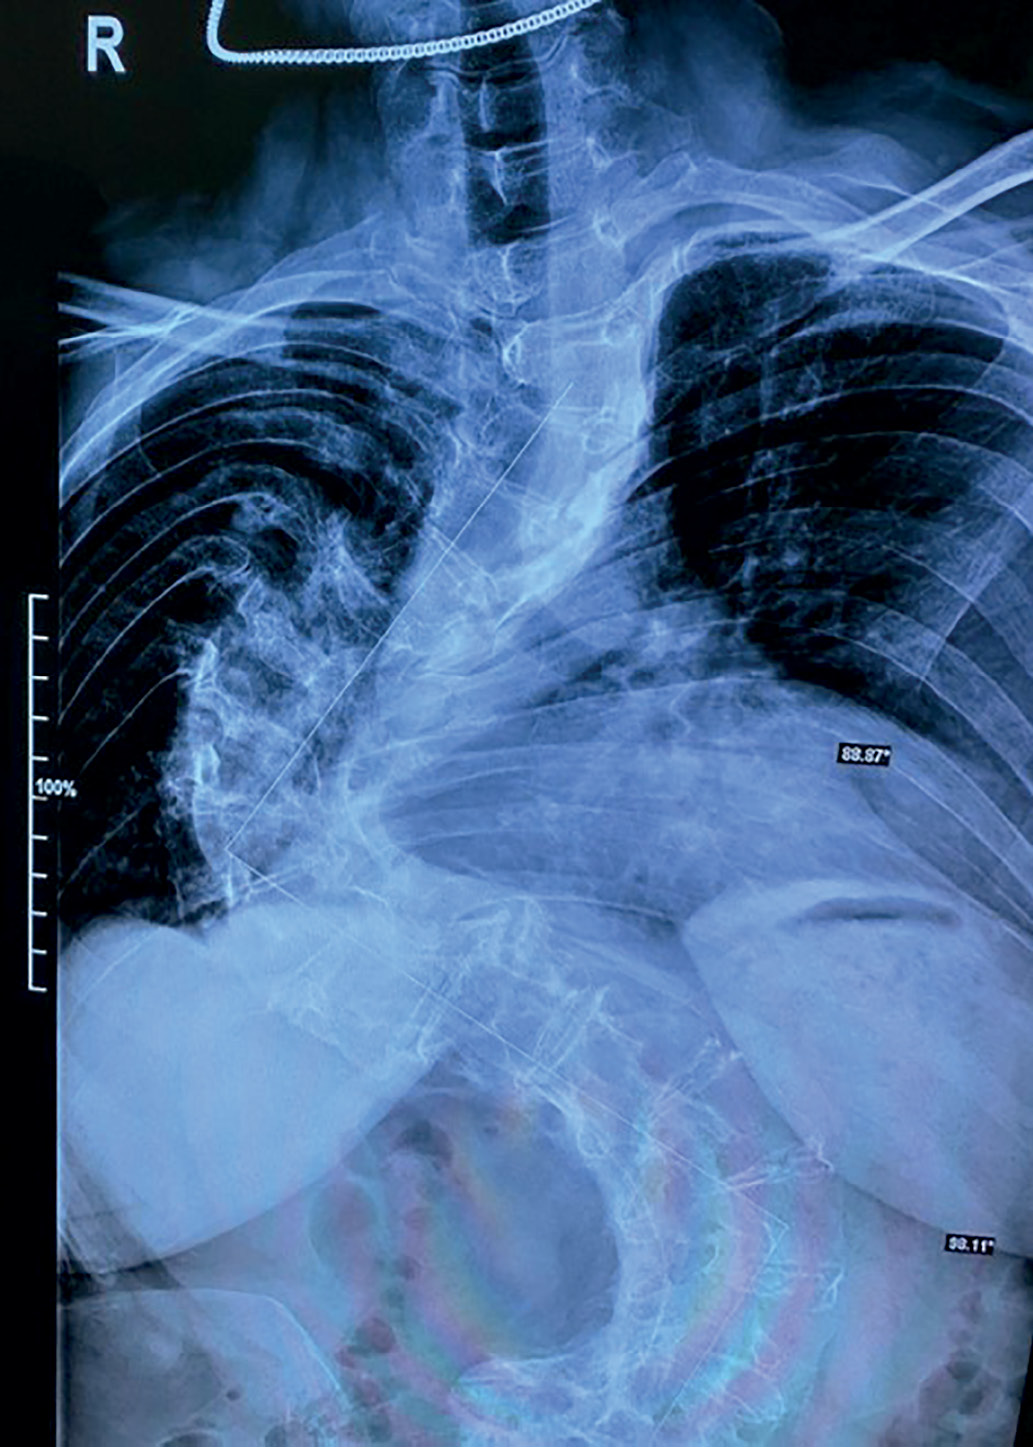

На представленной рентгенограмме грудного и поясничного отделов позвоночника, проведенной в этом году, отмечается значительное искривление грудного отдела позвоночника вправо с углом сколиоза 91° и столь же выраженное искривление поясничного отдела позвоночника влево с углом сколиоза 82° (рис. 1). Помимо этого, имеется ротация грудных и поясничных позвонков влево 1–2 степени, о чем свидетельствует визуализация правых реберно-позвоночных сочленений на уровне III–IV ребер, обычно незаметных в прямой проекции, и теней остистых отростков поясничных позвонков, смещенных резко вправо от срединной линии. Таким образом, рентгенологически определяется искривление позвоночника не менее чем в двух плоскостях.

Рисунок 1. Рентгенография грудного и поясничного отделов позвоночника.

Угол сколиоза (в данном случае соответствует сегментарному углу,

т.е. отклонению одного сегмента позвоночника от оси другого, прилежащего)

составляет почти 82° в поясничном и 91° в грудном отделе,

что указывает на максимальную, 4-ю степень сколиоза

(по классификациям Чаклина и Кобба устанавливается при значениях более 60°).